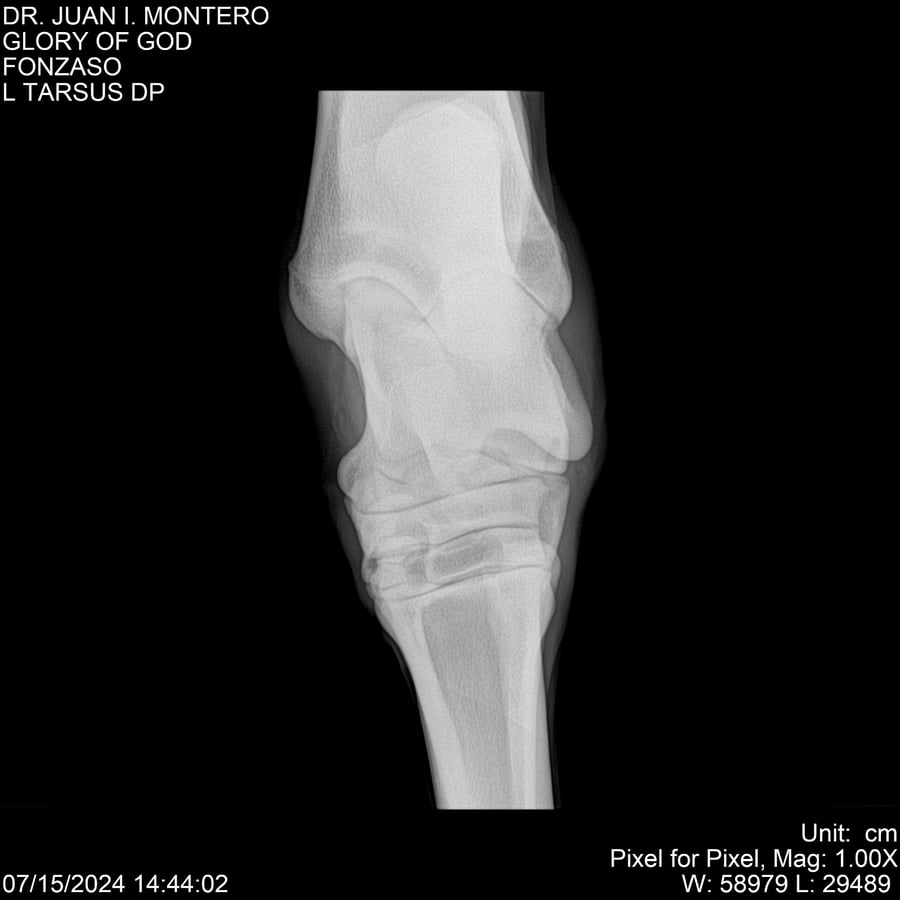

LOTE 10, GLORY OF GOD 🔥 🔥 🔥 Lote Anterior Volver al remate Lote Siguiente Ficha Contacto Montevideo - Ficha del Lote Identificador: #281389 Categoría: Yeguarizos Montevideo - 115 Visualizaciones ClicData Contacto Empresa: Abelenda N. R., Walter Hugo Nombre*: Teléfono* : E-mail* : Mensaje Enviar Registrese gratis Este contenido Exclusivo está disponible sólo para usuarios registrados Ingresar